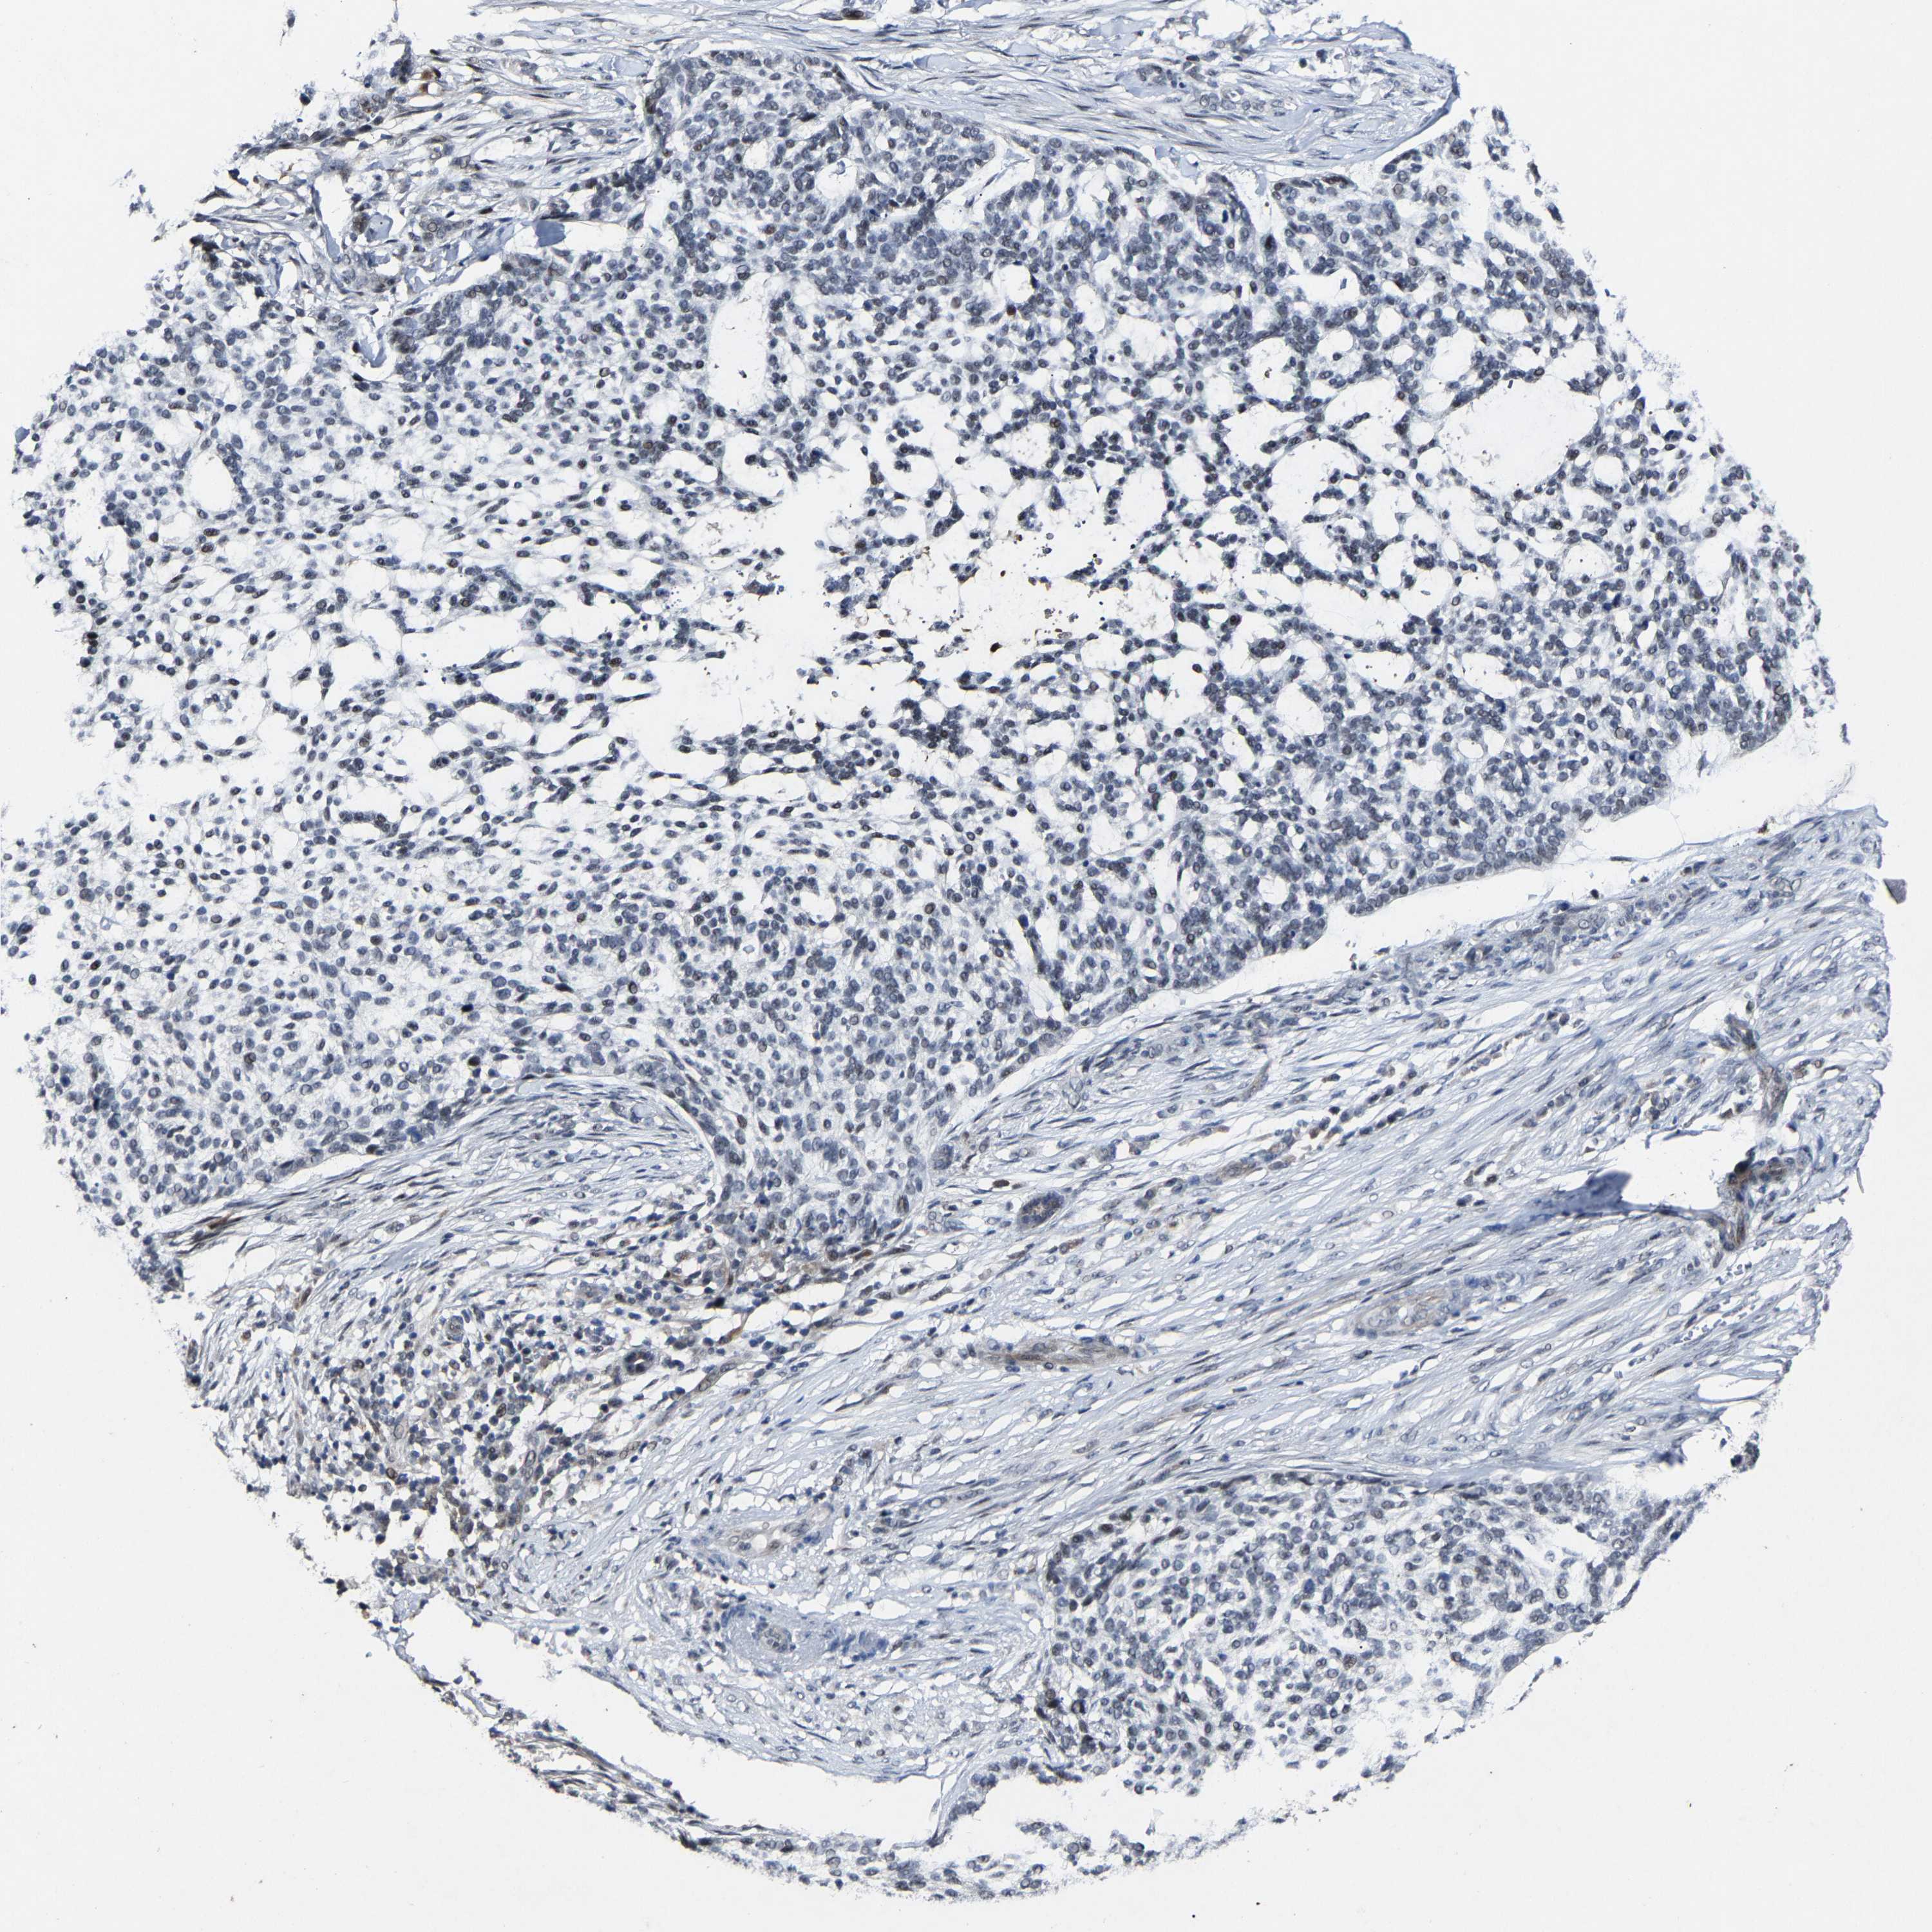

SKIN CANCER - Protein expressioni

A mouse-over function shows sample information and annotation data. Click on an image to view it in a full screen mode. Samples can be filtered based on level of antibody staining by selecting one or several of the following categories: high, medium, low and not detected. The assay and annotation is described here.

Antibody stainingi

Antibody staining in the annotated cell types in the current human tissue is reported as not detected, low, medium, or high, based on conventional immunohistochemistry profiling in selected tissues. This score is based on the combination of the staining intensity and fraction of stained cells.

Each image is clickable and will lead to virtual microscopy that enables deeper exploration of all samples and also displays staining intensity scores, fraction scores and subcellular localization as well as patient and tissue information for each sample.

Antibody HPA020116

Staining

Low

Intensity

Weak

Quantity

<25%

Location

None

Squamous cell carcinoma, metastatic, NOS